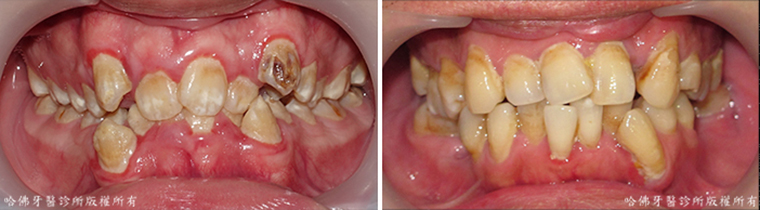

齒列不整,特別是存有牙齒擁擠的齒列不整,極易造成食物堆積的死角而引發蛀牙(圖2)。

(圖2)齒列不整,特別是存有牙齒擁擠的齒列不整,極易造成食物堆積的死角而引發蛀牙。藍色圈標定蛀牙位置。

當蛀牙尚在輕微的時候缺乏臨床症狀,蛀牙經常在嚴重時才出現酸痛腫脹等症狀。而當酸痛腫脹等症狀出現時,蛀牙已相當嚴重「而不」易治療(圖3)。

(圖3)當蛀牙尚在輕微的時候缺乏臨床症狀,蛀牙經常在嚴重時才出現酸痛腫脹等症狀。而當酸痛腫脹等症狀出現時,蛀牙已相當嚴重「而不」易治療。